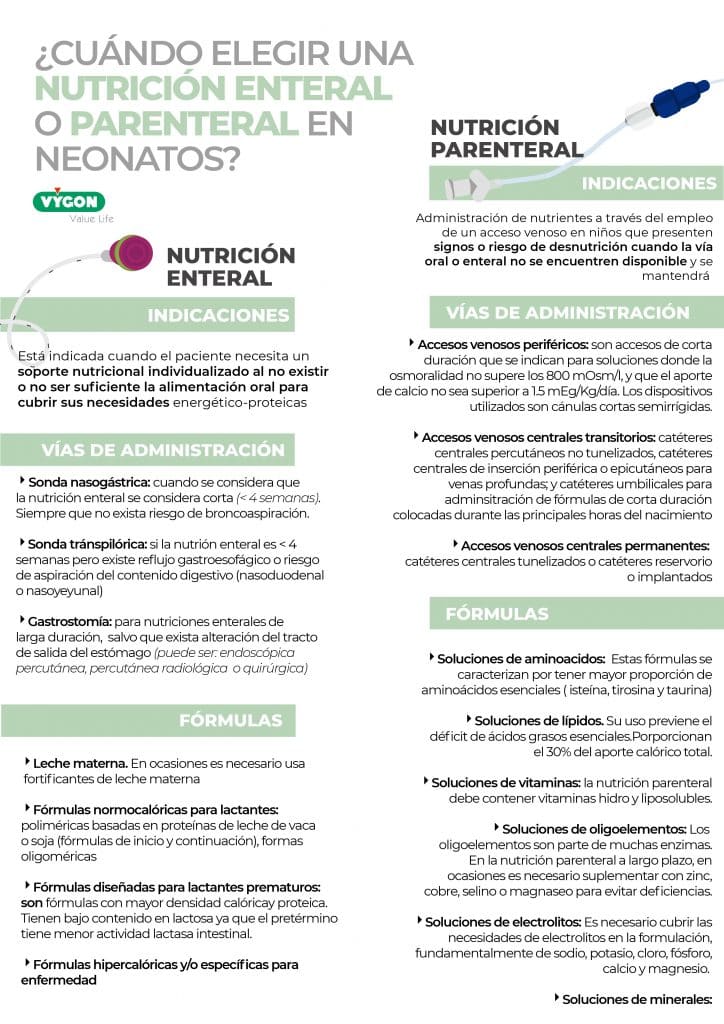

La nutrición enteral se define como un soporte nutricional cuyo objetivo es administrar la energía y nutrientes directamente mediante el tracto gastrointestinal. A excepción de la vía oral, se priorizará esta alternativa siempre que sea posible.

Está indicada cuando el paciente necesita un soporte nutricional individualizado al no existir o no ser suficiente la alimentación oral para cubrir sus necesidades energético-proteicas. Las principales situaciones clínicas en las que se dan estas características son (4,7):

Cabe indicar que la nutrición enteral apenas presenta contraindicaciones. No se podrá establecer como soporte cuando exista una obstrucción del tracto intestinal y su funcionamiento esté incapacitado. Además, debe darse una situación de estabilidad hemodinámica para poder comenzarla.

INDICACIONES PARA EL EMPLEO DE NUTRICIÓN PARENTERAL

La nutrición parenteral consiste en la administración de nutrientes a través del empleo de un acceso venoso con la finalidad de cubrir las necesidades metabólicas del paciente. Este soporte se empleará en niños que presenten signos o riesgo de desnutrición cuando la vía oral o enteral no se encuentren disponible y se mantendrá hasta que el paciente logre tolerar la alimentación por el método enteral.